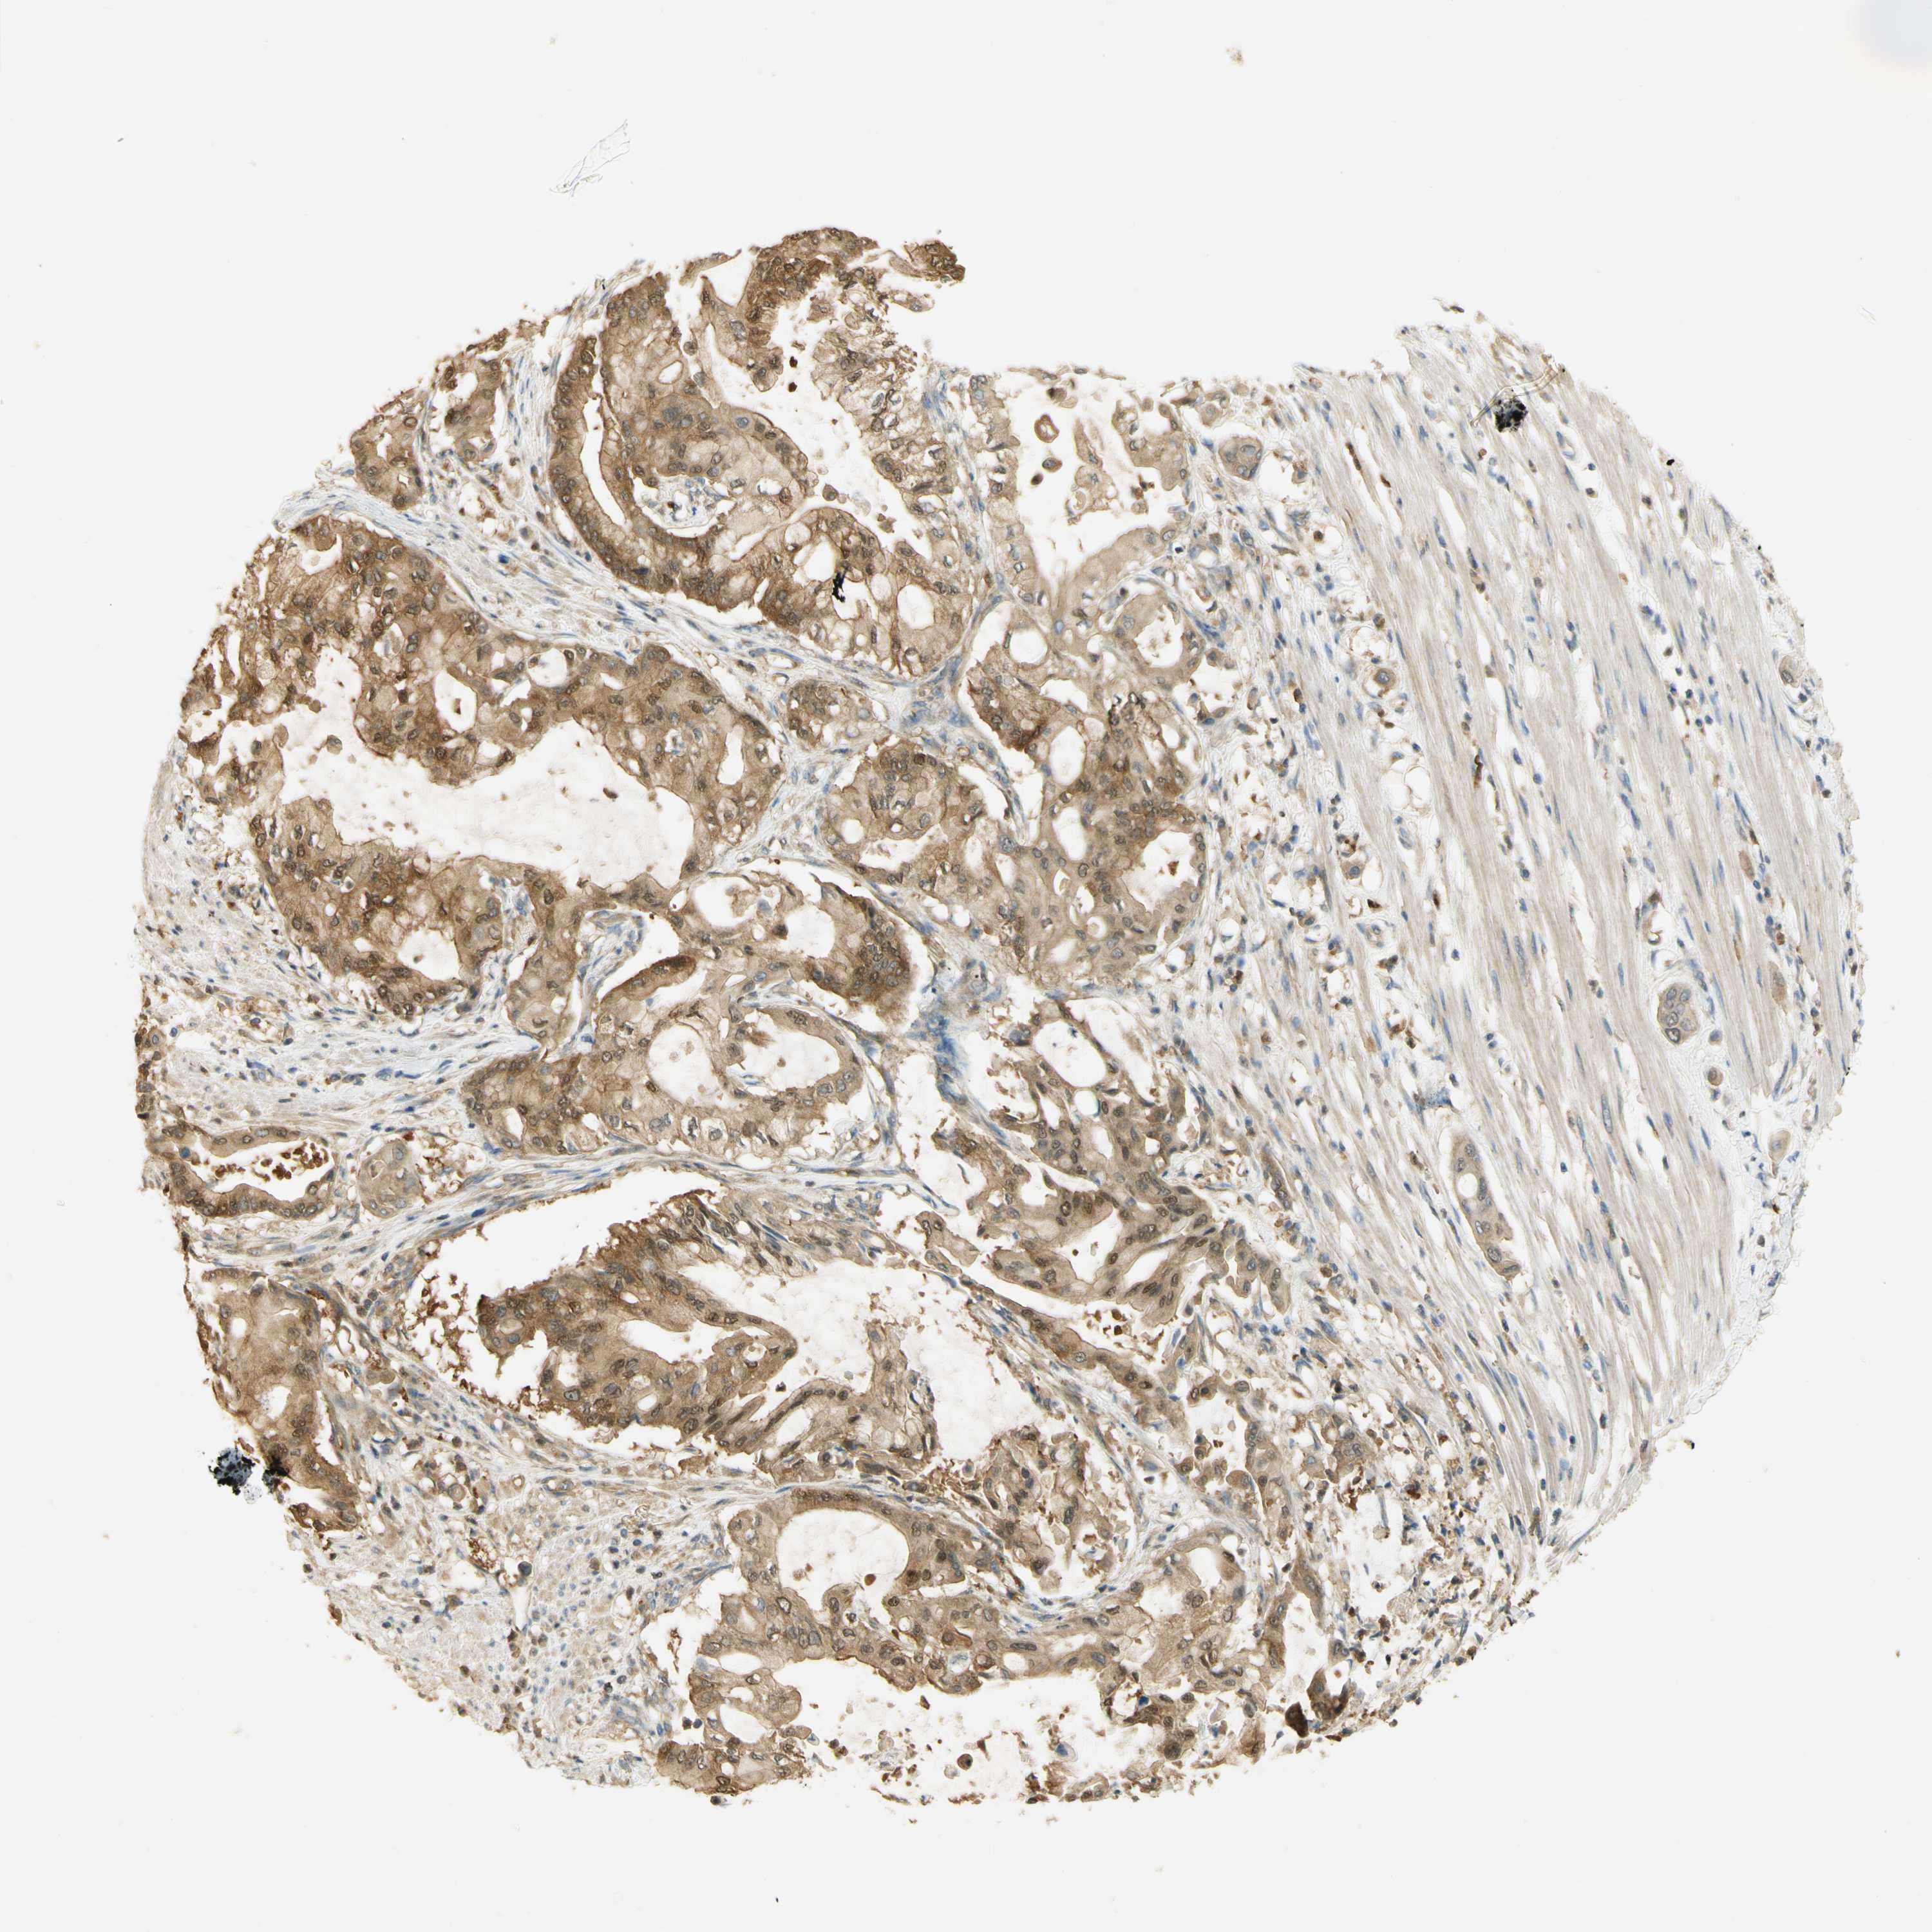

PANCREATIC CANCER - Protein expressioni

A mouse-over function shows sample information and annotation data. Click on an image to view it in a full screen mode. Samples can be filtered based on level of antibody staining by selecting one or several of the following categories: high, medium, low and not detected. The assay and annotation is described here.

Note that samples used for immunohistochemistry by the Human Protein Atlas do not correspond to samples in the TCGA dataset.

Antibody stainingi

Antibody staining in the annotated cell types in the current human tissue is reported as not detected, low, medium, or high, based on conventional immunohistochemistry profiling in selected tissues. This score is based on the combination of the staining intensity and fraction of stained cells.

Each image is clickable and will lead to virtual microscopy that enables deeper exploration of all samples and also displays staining intensity scores, fraction scores and subcellular localization as well as patient and tissue information for each sample.

Antibody HPA003565

Antibody CAB005312

Adenocarcinoma, NOS

Adenocarcinoma, metastatic, NOS